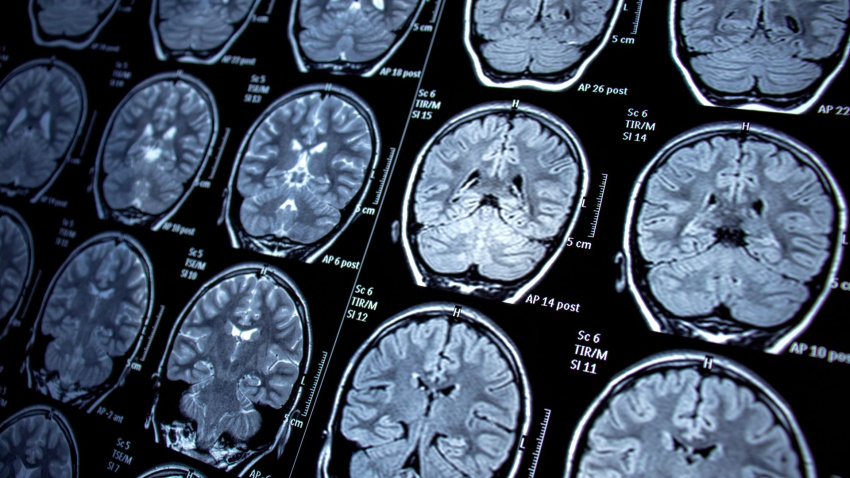

Con motivo del Día Mundial de la Epilepsia, la historia de Patricia Oria emerge como un testimonio de superación y esperanza. Entrevistada en el programa 'Herrera en COPE en Cantabria', esta mujer de 46 años ha relatado cómo ha sido su vida con una enfermedad que le fue diagnosticada con tan solo 8 meses y que hoy, gracias a una intervención, tiene completamente controlada.

En sus primeros años, las crisis eran principalmente convulsivas y se desencadenaban por picos de fiebre o alteraciones emocionales. Sin embargo, a partir de los 11 años, su condición cambió hacia las crisis de ausencia, uno de los tipos más frecuentes.

El punto de inflexión llegó a los 27 años, cuando se volvió farmacorresistente, es decir, la medicación dejó de hacerle efecto: 'Mi vida dio un giro espantoso', ha confesado, ya que pasó a sufrir crisis convulsivas cada mes y medio. Ante esta situación, fue derivada a la unidad de epilepsia del Hospital de Cruces, donde valoraron su caso para una posible cirugía.

La intervención quirúrgica, realizada el 13 de marzo de 2009, supuso un cambio 'totalmente' radical en su vida: 'A día de hoy no he vuelto a tener crisis; hace 7 años que no tomo medicación y no tiene nada que ver', ha celebrado Patricia. La operación significó pasar de una vida de incertidumbre, donde incluso un coche le destrozó un abrigo durante una ausencia, a recuperar la normalidad.